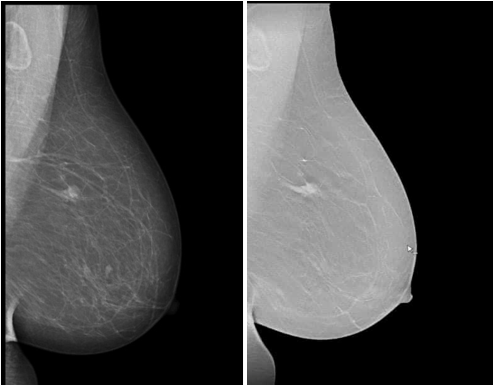

Mammography là phương pháp chụp X-quang đặc biệt, sử dụng tia X cường độ thấp chiếu vào các mô tuyến vú để thu lại hình ảnh tại tuyến vú. Qua hình ảnh thu được, bác sĩ có thể phát hiện các bất thường và khối u ở giai đoạn sớm ngay cả khi bệnh nhân chưa tự sờ thấy. Do đó, chụp nhũ ảnh được áp dụng rộng rãi để tầm soát với các trường hợp không có biểu hiện lâm sàng và giúp chẩn đoán với các trường hợp có các triệu trứng bất thường như sờ thấy khối u, chảy dịch núm vú, co kéo, tụt núm vú.

Hình ảnh chụp Mammography tuyến vú